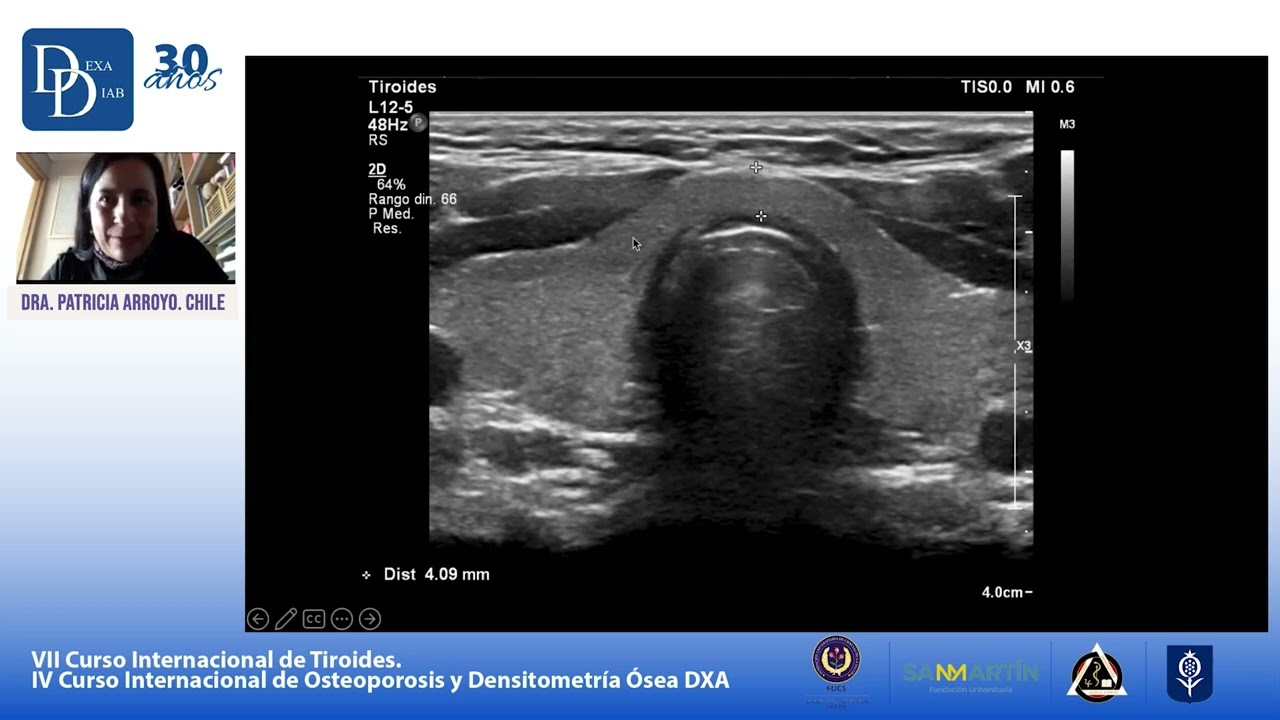

En esta videopresentación se describe la anatomía ecografíca de las glándulas salivares y su correlación con el diagnóstico por imágen seccional, así como los hallazgos ecográficos en la patología más habitual de las glándulas salivares.